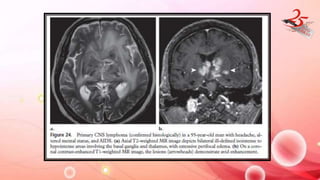

PRIMARY CNS LYMPHOMA

• CAUSE : immunocompetent and immunocompromised

IMAGING FINDINGS:

• T2 hypointensity and high attenuation in CT involves deep

hemispheric periventricular white matter, corpus callosum, and

basal ganglia

• MRS : Elevated choline levels

• Immunocompetent : Solid, homogeneously enhancing lesions

• Immunocompromised : Ring enhancement and central necrosis